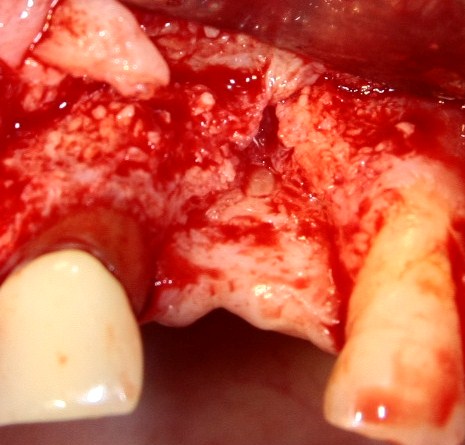

Делаем разрез в пределах кератинизированной десны. Скелетируем кость, видим следующее:

По краям от лунки видны остатки прошлых операций. Это не кость, а грануляции вперемежку с твердыми частичками биоматерила. Жди мы хоть несколько лет — вряд ли они организовались в приемлемую для имплантации костную ткань. Поэтому мы всё вычищаем, до естественной кости:

Ее объем, как мы видим, небольшой, использовать его для ПРАВИЛЬНОЙ установки импланта нереально. Почему выделил слово «ПРАВИЛЬНОЙ»? Потому что некоторые типы имплантационных систем позволяют установить имплантат хоть куда, хоть в какой объем кости, если очень хочется, конечно. Но ведь у нас нет задачи «воткнуть» имплантат всеми правдами и неправдами, верно? Комплексная цель лечения — воссоздание полноценно функционального зуба со всеми окружающими тканями. Чем мы, собственно, и занимаемся.